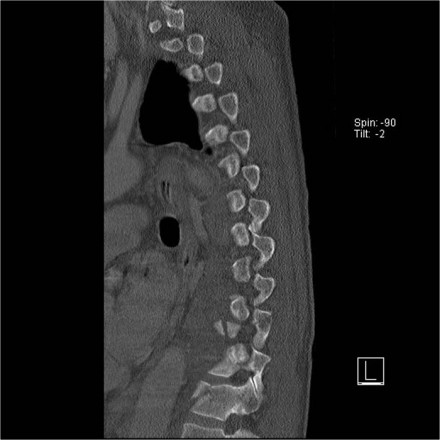

Rigid spine

Patients with a rigid spine (such as in ankylosing spondylitis, DISH and rheumatoid arthritis) are more susceptible to spinal fractures, even after minimal trauma (6).

Ossification of the spinal ligaments and calcification of the annulus fibrosus alter the biomechanics of the spine, creating long lever arms and limiting the ability to absorb even minor impacts.

The bone is usually very osteoporotic.

The images are of a patient with a typical bamboo spine as a result of ankylosing spondylitis.

After a fall on his back no fracture was seen on the x-rays.

However the CT shows a thin fracture line through the anterior side of the vertebral body and also through the spinous process.